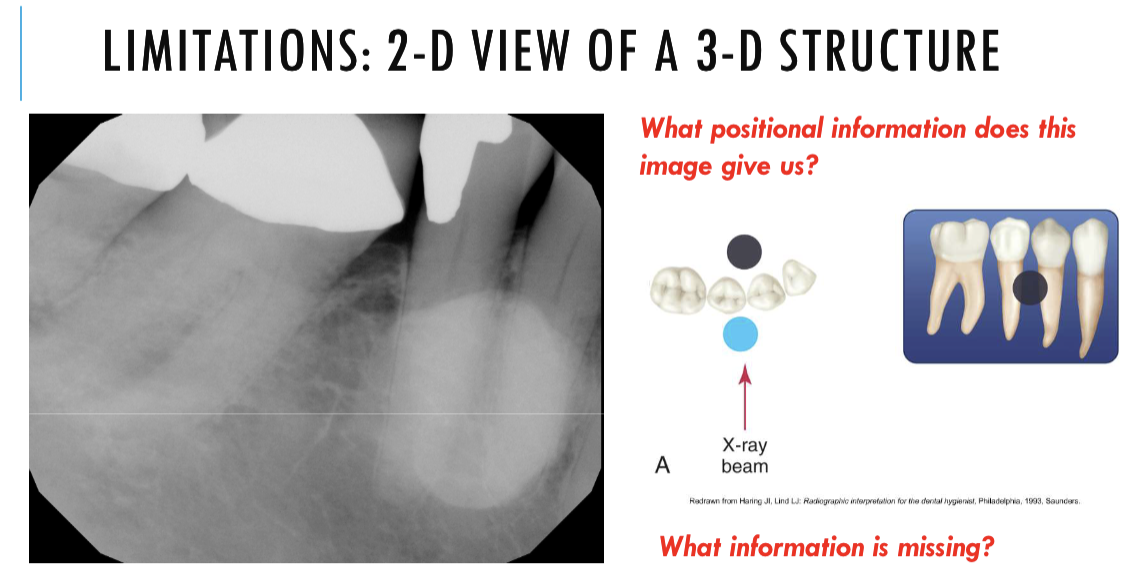

can tell us how forward how far back or how inferior or superior

can tell us anterior or posterior

but cant like us inferior or superior

unable to assess from this single image the objects buccal-lingual position relative to the teeth